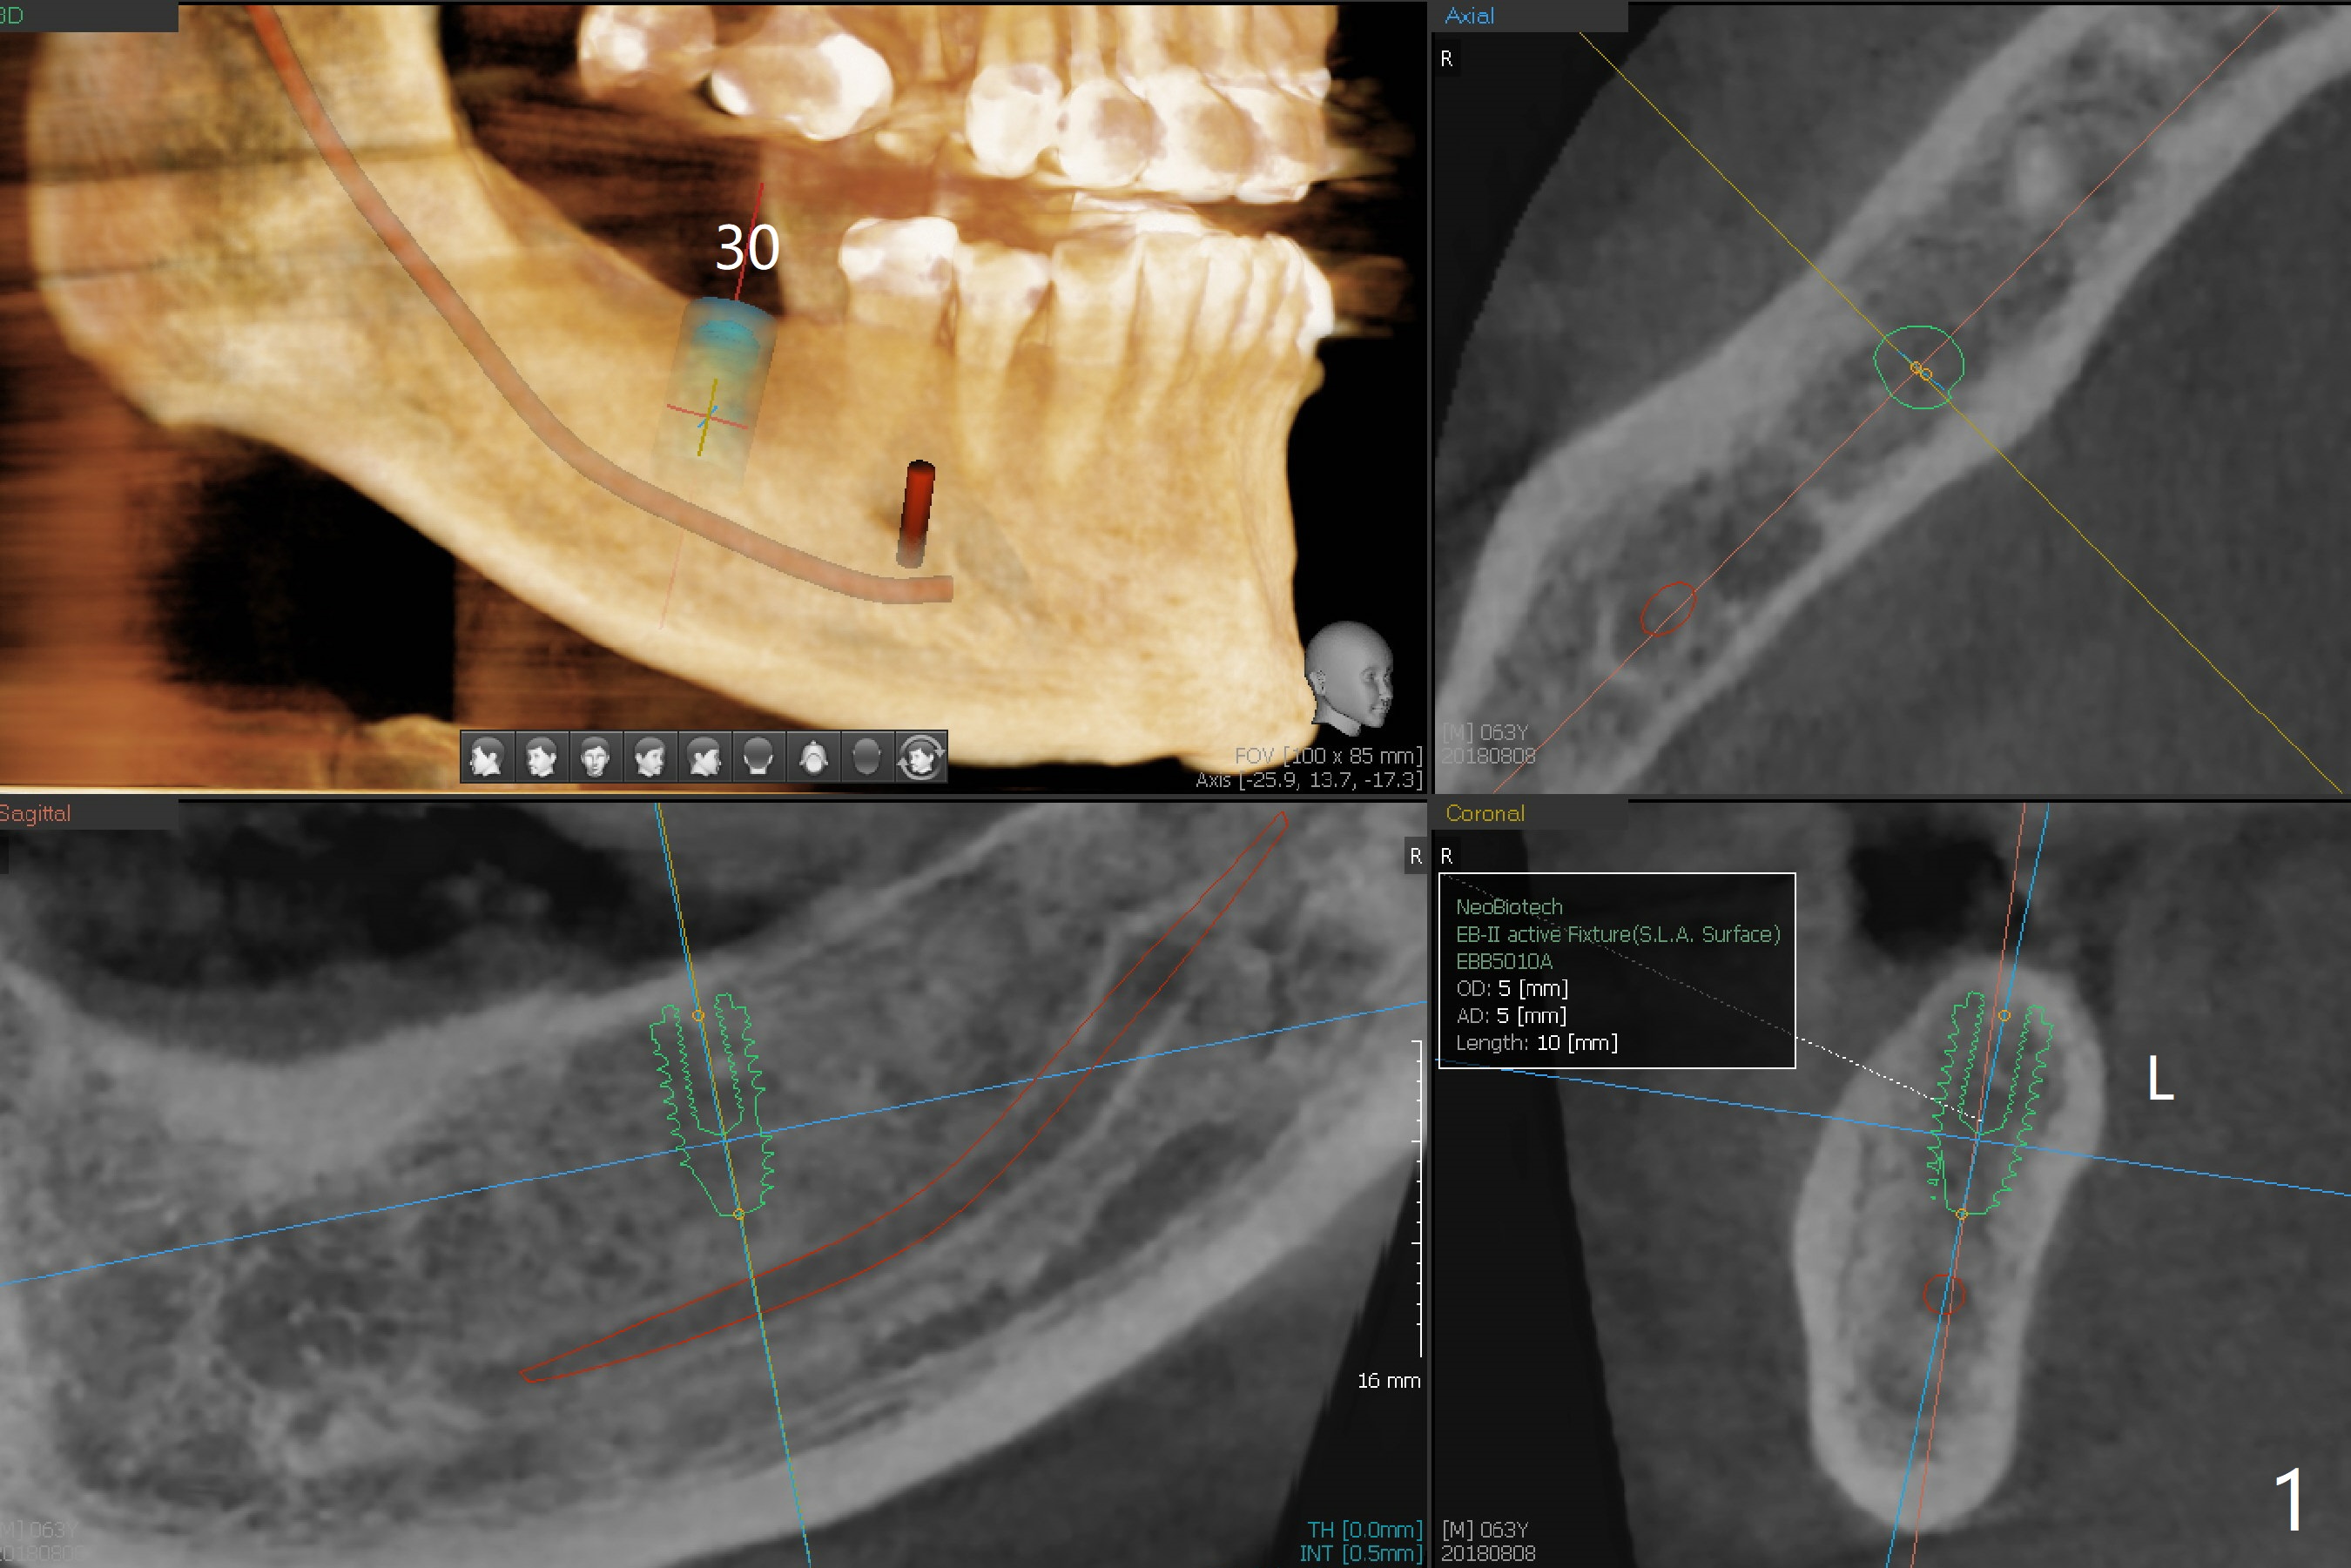

A 63-year-old man agrees to have an implant at #30 with guide 7 months post cementation of a crown at #3. For convenience, add an additional sleeve at #31 as long as there is enough vertical restorative space in case he changes his mind in the near future.